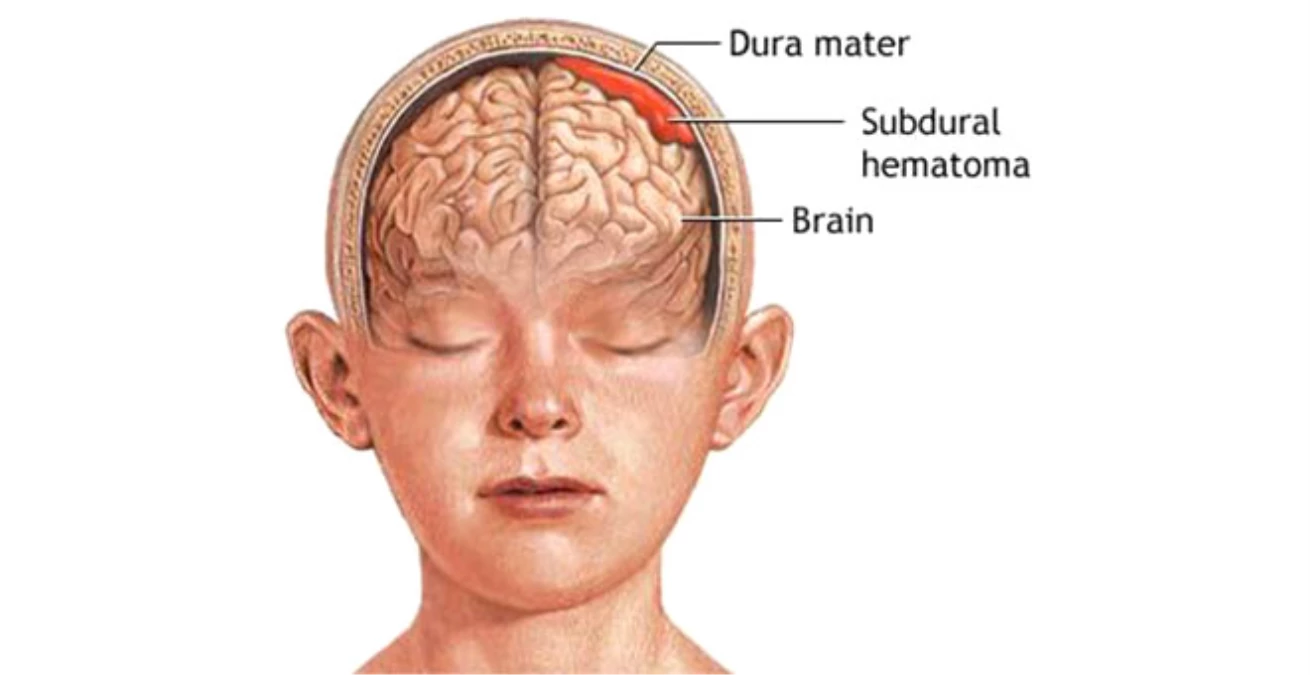

Медицинские аспекты и диагностика субдуральной гигромы мозга